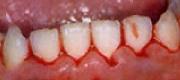

【ケース3】 歯肉炎の治療例

【治療前】

【治療後】